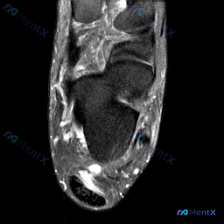

整理了一份足踝MRI读片病例,分享下分析思路,大家可以一起讨论。 病例影像基础信息 这是一张足踝部T2加权矢状位MRI,显示跟骨、距骨、部分跗骨和足底结构: - 骨骼:跟骨和距骨骨髓信号基本正常,皮质边缘清晰,未见明显异常信号 - 关节:跟距关节间隙清晰,无明显关节面侵蚀或严重狭窄 - 异常发现:跟...